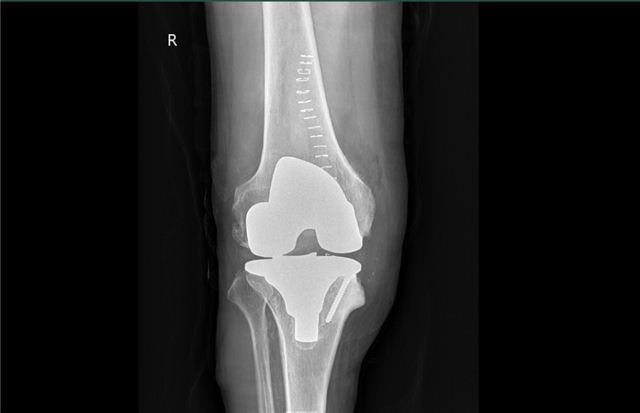

经过详细的术前规划,手术择期进行。患者的内侧平台缺损通过螺钉打桩来解决,内侧副韧带过紧通过骨性缩容、袖套样剥离、拉花来达到平衡。手术台上的这一幕像极了2年前师傅带我做手术的样子,主刀位的师傅和助手位的我,而如今,看着助手位我带教的徒弟一丝不苟学习的样子,这可能就是帮扶的意义吧,让更多先进的技术在本地生根发芽、枝繁叶茂,最后长成能独立为本地百姓遮风挡雨的“杏林”。

两个小时后,我和我的徒弟顺利完成手术,在手术台上将我所学到的交棒给我的徒弟,希望他在面对非常规手术时能有更多的选择。

术后病人非常满意,以前他畸形的腿变直了,也可以正常弯曲了,可以像正常人一样行走,他还在期待另一侧的手术。

术后X片